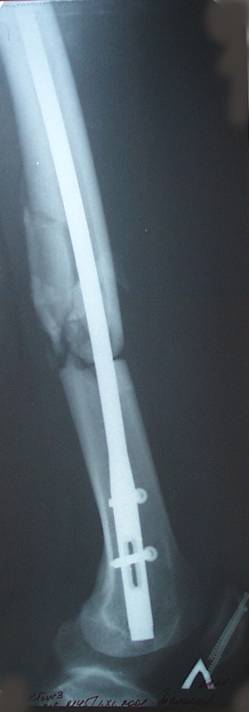

Уважаемый Сергей, избрав вариант DHS плюс ретроградный гвоздь Вы явно обезопасите себя от проблем, связанных с введением штифта через trochanteric fossa. Очень это может быть проблематично, Вы правы. Поэтому DHS плюс ретроградный гвоздь - спокойно выполнимый вариант, особенно в "чужом" отделении. Схожий свой случай из далёкого теперь уже 1999г. прилагаю, только вместо канюлированных винтов у Вас будет DHS (VHS). А если антеградный гвоздь - то только из тех, что предназначены к введению через верхушку вертела. И это тоже выполнимо, но сложнее. Мне так кажется.